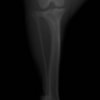

術前正面像

左後肢の挙上を主訴に来院されました。触診にて両関節の前方引き出し兆候、両膝蓋骨の内方脱臼を認めました。関節液検査より免疫介在性多発性関節炎は否定的でした。レントゲン検査にてfat pad signを伴う関節炎が認められたことから、前十字靭帯断裂と膝蓋骨内方脱臼(左GradeⅢ 右GradeⅢ〜IV)併発と診断し、手術を行いました。

手術は片足ずつ行い、両膝とも術中の関節鏡検査にて前十字靭帯の完全断裂と半月板損傷を確認しました。TPLO、半月板切除と滑車溝形成を始めとした膝蓋骨脱臼整復術を実施いたしました。膝蓋骨の安定化を測るために外側支帯を強固に縫合し、内側支帯は切除し縫合せずに開放状態にしています。

術前のTPAは左後肢33.1°右後肢26.8°でしたがTPLO実施により左後肢5.5°右後肢12°に矯正されました。